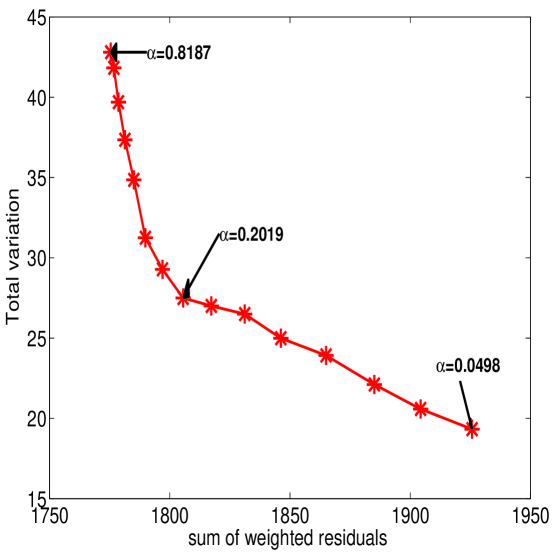

Regularization constant : There are many approaches for determining the choice of an appropriate regularization constant . A good reference would be [24] in which the methods of unbiased predictive risk-estimation, generalized cross validation, and the L-curve are described. In general, the choice of depends on the noise level of the problem. Here balances the homogeneity of the uptake rate against the residual of the traditional Patlak least squares data fit. For the PET imaging application, noise in the TTAC data depends on the scanner, the reconstruction method, the tracer dosage and even the kinetics of individuals. It is therefore possible to make a standard parameter setting for commonly-used environments. The most convenient method for the selection of is the so-called L-curve, [10, 11], which plots total variation against for all tested . The L-curve clearly displays the compromise between of the homogeneity and the residual of the Patlak fitting equations. The corresponding to the left lower corner of the L-curve is considered as the optimal choice. One representative L-curve of our simulations is illustrated in figure 6. We found for our simulations that a suitable choice is , but certainly it will in general depend on the reconstruction algorithm. For example, the simple EM method and filtered backprojection algorithms introduce more noise than the maximum a posteriori (MAP) algorithm, [8, 1]. For real data not only are there additional sources of noise but the choice for will also depend on the specific tracer. However, once an appropriate is found by L-curve for a specific imaging environment, it can be fixed for future imaging calculations.

Figure 6: L-curve for the simulation case ‘+4+’. Total variation against the sum of weighted residuals, i.e. , for from to is plotted. is associated with the left lower “corner”. -